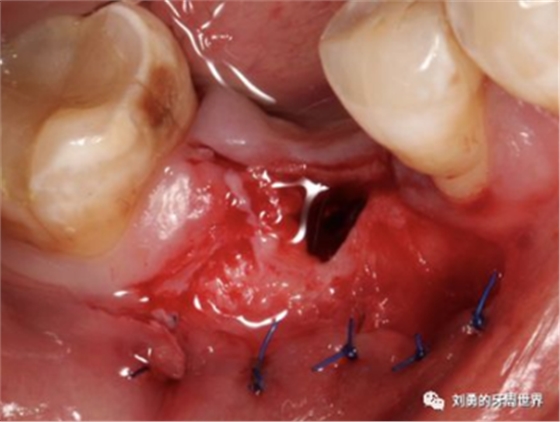

第四個要說的選擇就是受區(qū)翻開的半厚瓣可以有兩種處理方式,一種是根向移位縫合固定在根向的骨膜上,還有一種簡單的方式就是把這個半厚瓣剪掉扔掉。本人在臨床上喜歡兩個方法結(jié)合使用。

縫合方法的好處是受區(qū)可以更好的止血,但是缺點是操作困難,

剪掉方法的好處是操作簡單,但是缺點是增加受區(qū)出血。

比如下面兩張圖就分別是縫合和剪掉的方法: